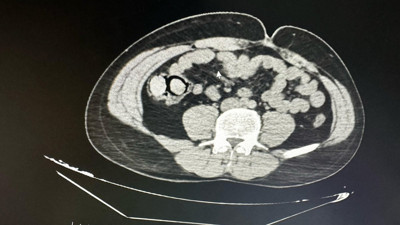

Midelerinden zehir çıktı Bingöl’de akıllara durgunluk veren bir olay gerçekleşti. Otobüs yolculuğu sırasında polis ekiplerince durdurulan yabancı uyruklu iki şahsın midesinden 10 parça halinde 113 gram metamfetamin çıktı.

Mide ve bağırsaklarından 51 kapsül uyuşturucu çıktı Samsun’da yakalanan zanlının mide ve bağırsaklarından 51 kapsül uyuşturucu çıktı.

Midesinde uyuşturucu taşıyan İranlı, havalimanında yakalandı İran'dan Samsun'a gelen İran uyruklu Matin M.'nin midesinde poşete sarılmış, 10 adet olmak üzere toplamda 191,18 gram metamfetamin ele geçirildi.

Yabancı uyruklu şahsın midesinden tam 53 paket çıktı. Nasıl girdiler ülkeye? Gümüşhane’de yolcu otobüsünde yol kontrolünde şüpheli hareketlerde bulunan bir yabancı uyruklu şahsın midesinden tam 53 paket (513,08 gram) metamfetamin çıktı.